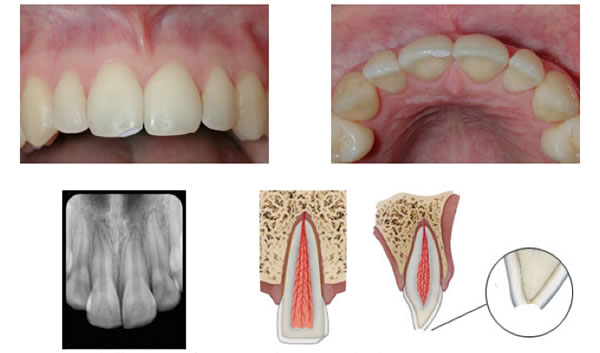

Crown fracture

Figure 2. A shallow crown fracture involving enamel only.

Figure 3. A crown fracture involving both enamel and dentin but without exposure of the pulp.

Crown fractures are the most commonly reported dental injuries, characterized by fractures of the enamel (Figure 2) or enamel and dentin (Figure 3) . There is a loss of tooth structure but no pulpal exposure. The goal of treatment is to close the dentinal tubules to prevent entry of microorganisms and to address patient discomfort. If there is a clean break and the crown fragment is retrieved in tact, it can be simply re-attached to the tooth structure via dentin bonding agents.

The risk of pulpal inflammation and necrosis is generally low but becomes more of a factor if the fracture approaches within close proximity of the pulp. As a general rule, if there is less than 0.5mm of dentin protecting the pulp chamber, it is advised to place a protective glass ionomer liner to close the dentinal tubules, followed by dental adhesives and composite resin. Sealing the dentinal tubules is critical, as it prevents the passage of microbes from the oral cavity into the pulp, which can lead to a strong inflammatory response and eventual pulpal necrosis. GI cements are advantageous as they can also be bonded without etching, which simplifies the clinical procedure and avoids further pulpal inflammation from the conditioning process. The material is also very biocompatible and is oftentimes utilized as a perforation repair or direct pulp capping agent.